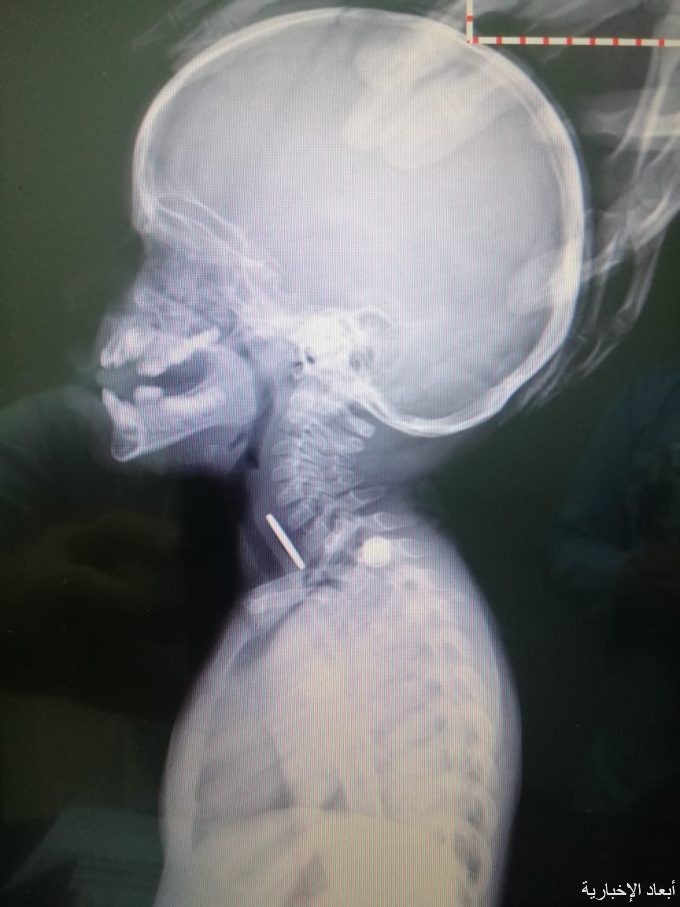

تمكن أخصائي جراحة الأنف والأذن والحنجرة بمستشفى الأمير سلطان بمليجة الدكتور أحمد فارس من استخراج قطعة معدنية من الجزء العلوي لمريء مراجعة كويتية تبلغ من العمر عامين بعد أن حضرت للمستشفى برفقة والديها.

وأفاد والد الطفلة بابتلاع ابنتة لجسم غريب، وبعد إجراء الأشعة والفحوصات اتضح وجود جسم غريب من المريء، ليتم الفور تجهيز غرفة العمليات وإدخال المريضة لإجراء العملية تحت التخدير العام، حيث تكللت بالنجاح وتم استخراج القطعة المعدنية التي كانت عبارة عن عملة نقدية من فئة ٢٥ هللة، كما تم تسجيل خروج الحالة بعد تحسنها والاطمئنان عليها.